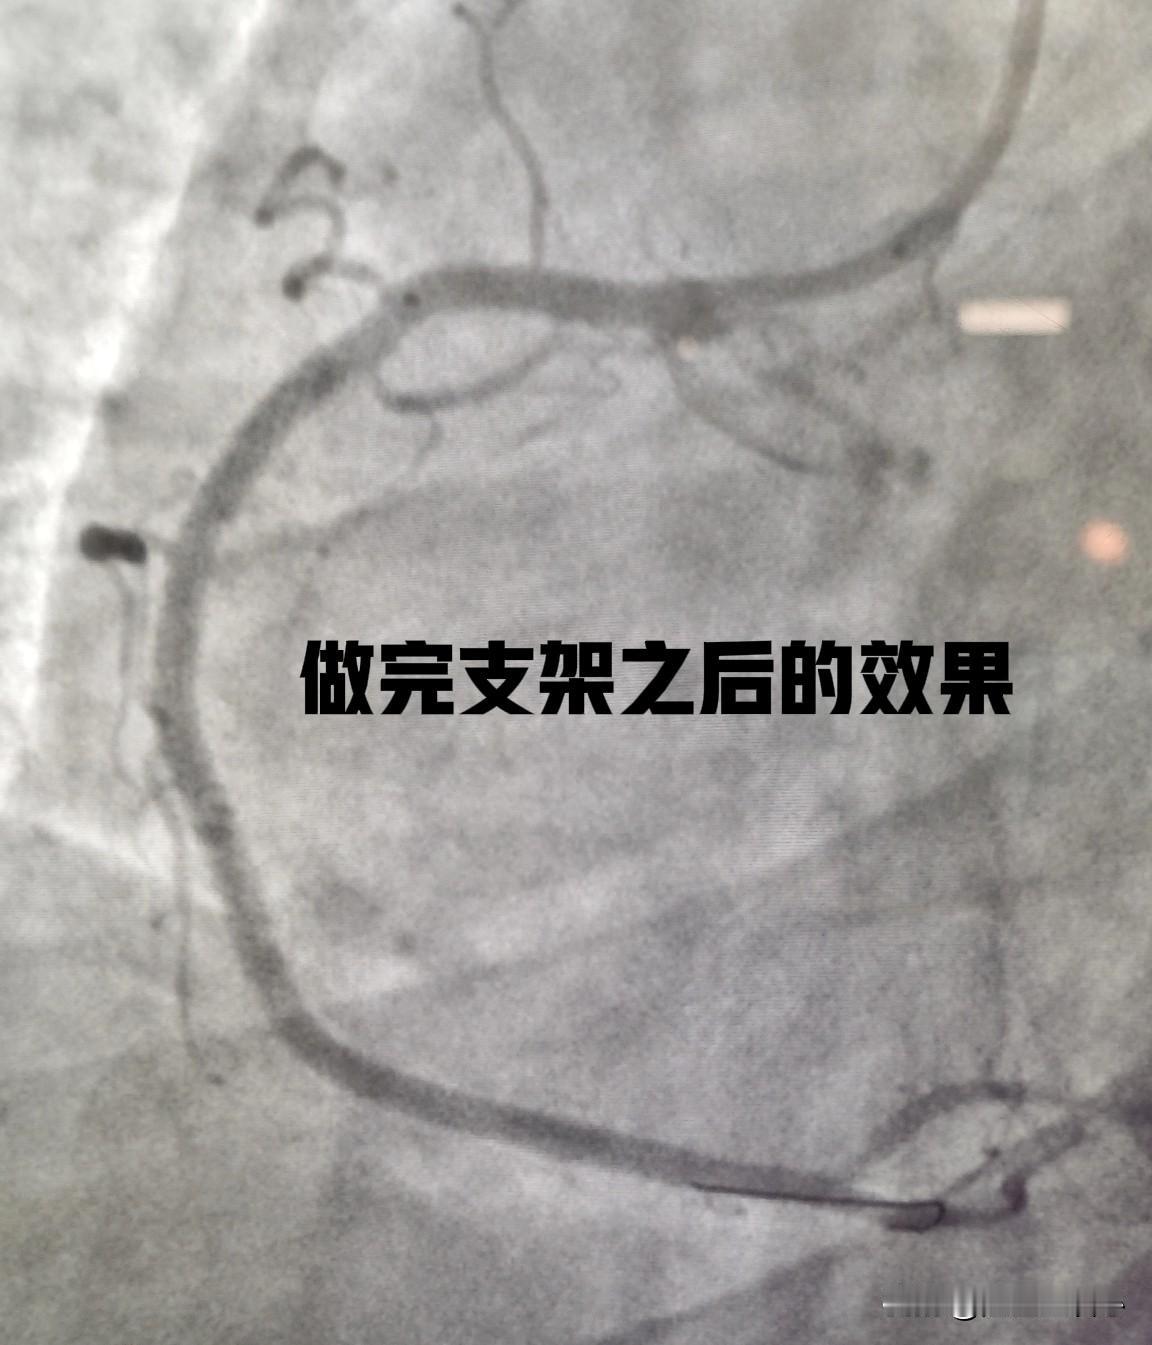

这是一个53岁男性患者,做了冠脉CTA检查发现右冠状动脉重度狭窄,入院以后复查了冠脉造影(如图1),显示右冠近段重度狭窄,远端完全堵塞了,远端血管无法供血。选用SAL0.75的指引导管,在微导管的支持下,用导丝通过病变(如图2)。直径1.5mm的球囊扩张近段重度狭窄段后,造影发现远端血流仍然没有显示(如图3)。这时直接冠状动脉内注射了硝酸甘油,精准给药,直达冠状动脉。几秒钟后再次造影发现,远端血管瞬间通畅,血流完全恢复。最后在近段植入2枚支架(如图4)。